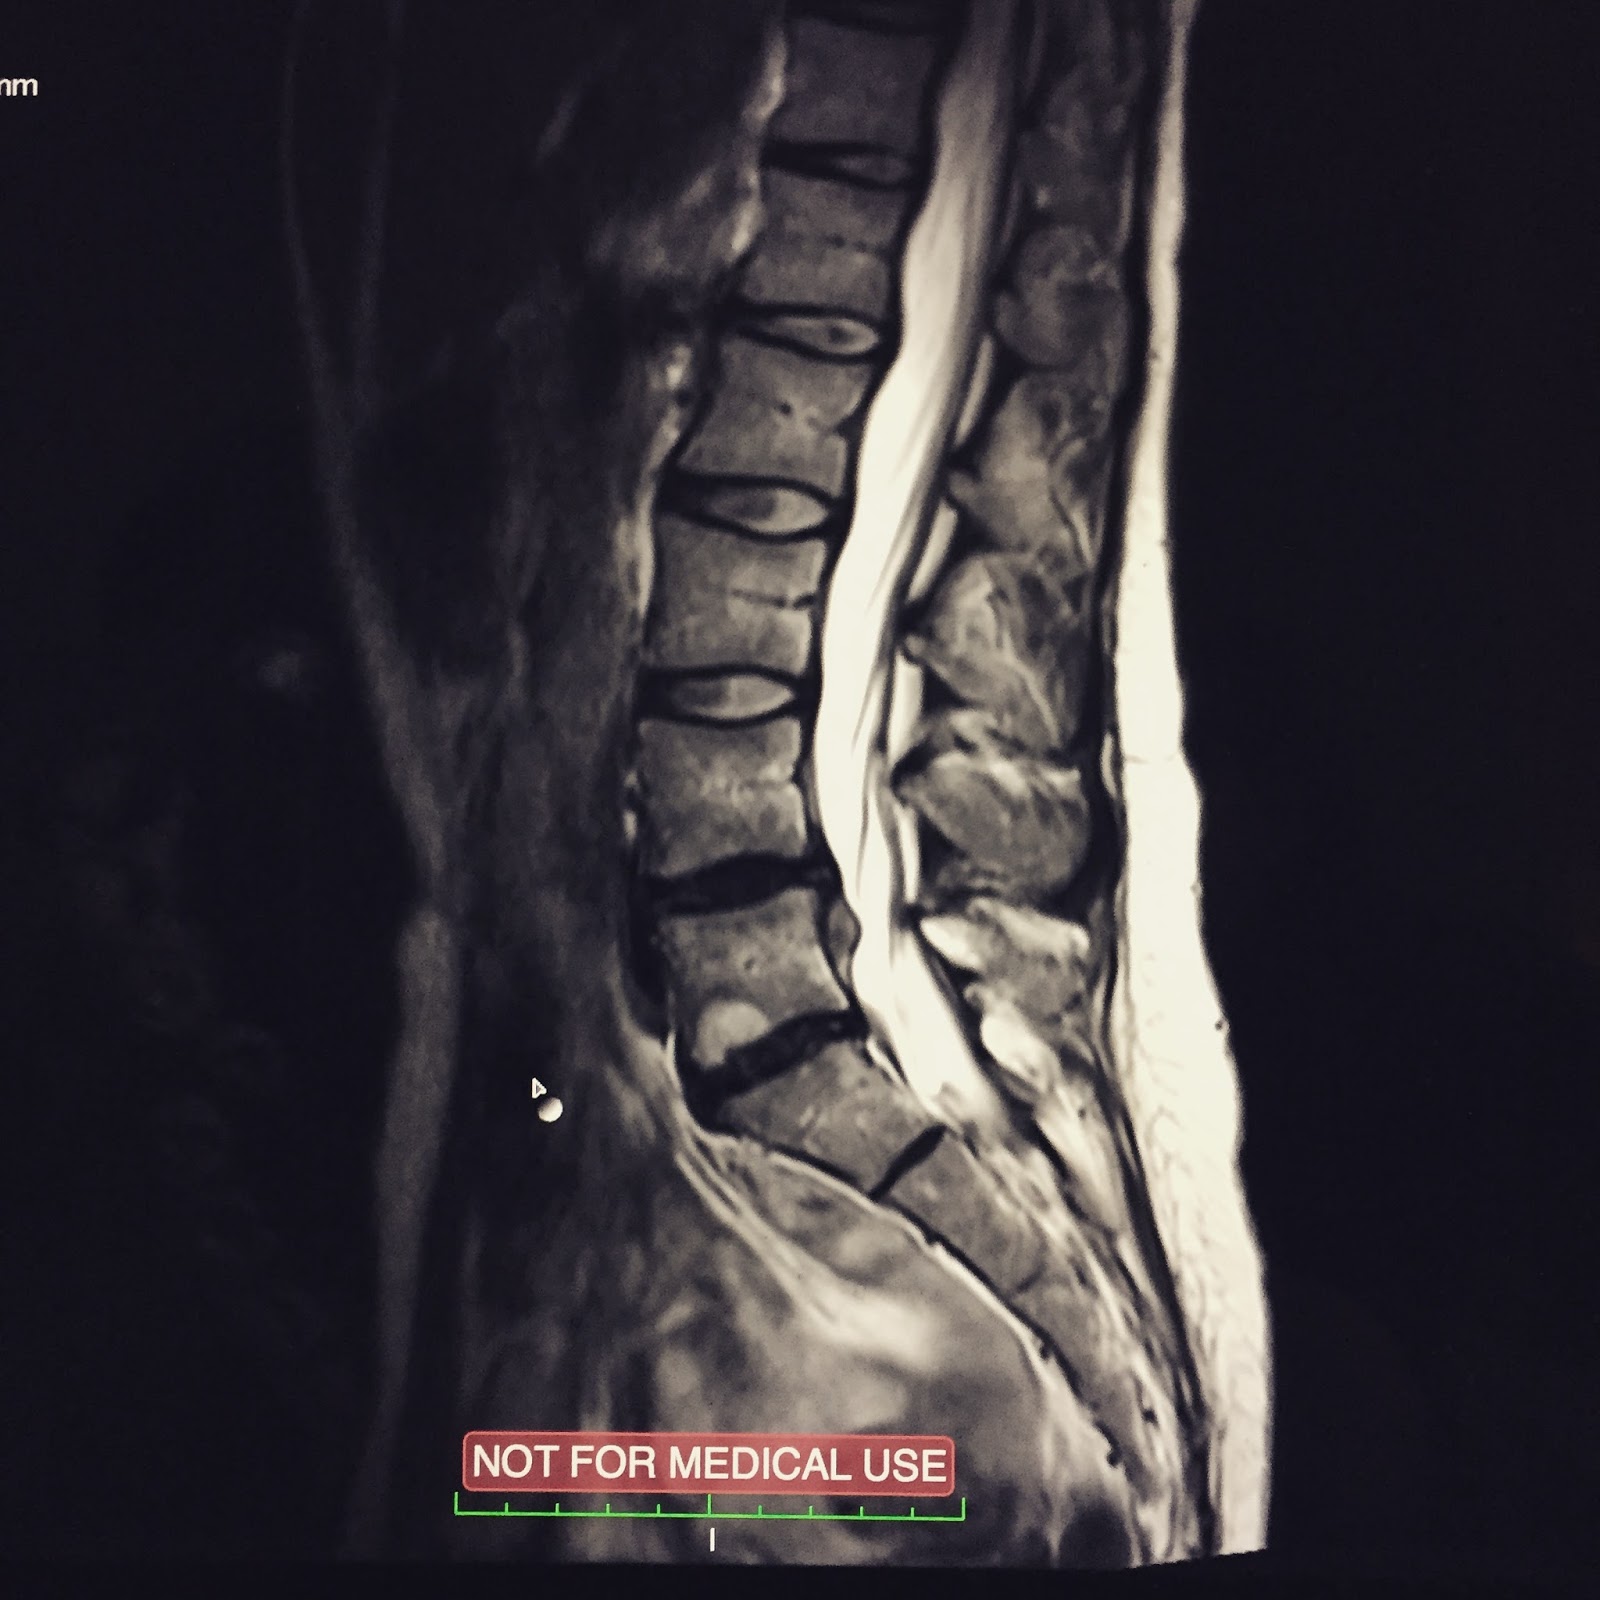

| Siinähän se näkyy. |

Leikkauksen arvoisia vai ei? Lääkäri tuijotti magneettikuvassa näkyvää välilevyn pullistumaa ja oli sitä mieltä että kyllä varmaan pitää leikata (ylläri).

Se painaa hermojuurta. Ja kyllähän se haittaa sun elämää, sähän et voi kumartua.